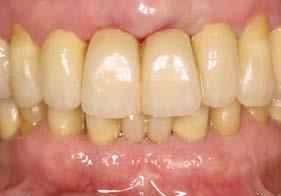

Pasadas 4 semanas, se colocaron los implantes dentales en un momento en que se observaba regeneración ósea incipiente y cierre completo de los tejidos blandos. Tras un periodo

de osteointegración de 6 meses en el maxilar y 3 en la mandíbula, se inició la fase protésica definitiva. En ese momento, la opción preferida fue el uso de pilares personalizados cementados con recubrimiento cerámico. Esta alternativa terapéutica fue la elección para lograr una correcta estética y un sellado adecuado prótesis-implante, con un menor número de complicaciones asociadas. Actualmente, se optaría por una prótesis atornillada, debido a sus ventajas en cuanto a posibilidad de retratamiento, sellado y control de los tejidos.19-21

En la zona anterior maxilar se realizaron pruebas estéticas detalladas, optimizando aspectos como líneas medias, troneras y pónticos (Figura 6-8). En el arco inferior, se conservaron los

Figura 5. Aspecto intraoral posterior a las extracciones y a la ferulización de los dientes remanentes en el sector anterior superior, con el objetivo de mantener la estética durante la cicatrización. Las piezas conservadas fueron sometidas a tratamiento periodontal mediante raspado y alisado radicular, seguido de un programa de mantenimiento y control riguroso de placa en el postoperatorio.

caninos y premolares mediante tratamiento periodontal intensivo. Esta decisión favoreció la integración funcional de dientes e implantes, manteniendo la propiocepción y mejorando el control de posibles sobrecargas funcionales como el bruxismo.22-24

Figura 6. Prueba de los postes y ajustes hasta lograr una correcta estética de la prótesis sobre implantes.

Figura 7. Colocación de la prótesis

Figura 8. Imagen de sonrisa con la prótesis finalizada.